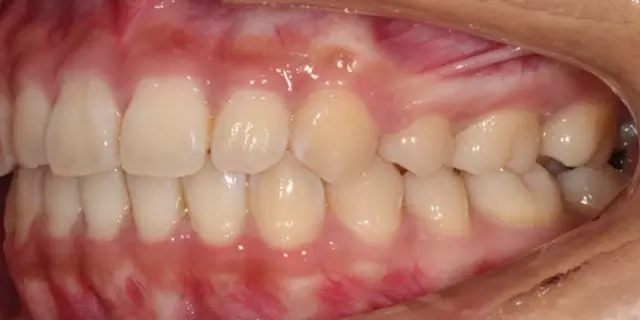

Damon 病例分享:安氏 II 類(lèi)二分類(lèi)露齦笑的矯治(董一磊)

治療前后對(duì)比